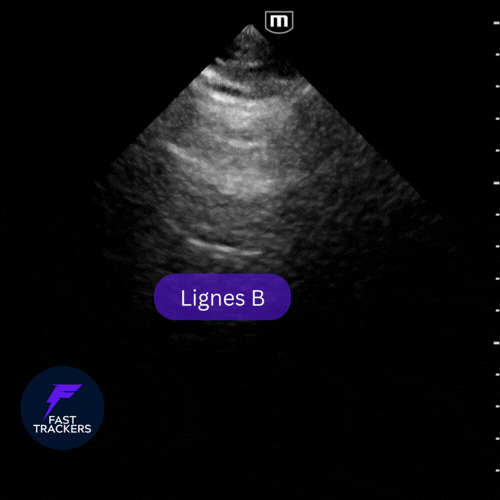

Les lignes B sont des artefacts verticaux fins, brillants, qui partent de la ligne pleurale et atteignent le fond de l’écran en effaçant les lignes A.

Elles bougent au rythme du glissement pleural et ressemblent à des faisceaux lumineux de projecteurs au plafond.

Forme normale

• Peu nombreuses (1 à 3 max par champ).

• Situées surtout dans les zones déclives (bases pulmonaires) – plus fréquemment observées chez les personnes âgées.

• Mobiles et fines.

Rappel : jusqu'à 3 lignes B par champ = physiologique. +3 lignes = pathologique.